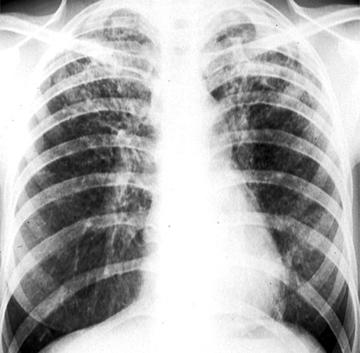

继发性肺结核

继发性肺结核(英文名:secondary pulmonary tuberculosis)是指肺内已静止的原发病灶重新活动(内源性),或外界结核分枝杆菌再次吸入肺部(外源性)而发生的肺结核病。这是肺结核病中最常见的类型,多位于双肺上叶和下叶背段。[2]继发性肺结核可于原发感染后的任何年龄段发生,最常见于成年人,故又称成人型肺结核。[3]

继发性肺结核病理改变有渗出性病变、增生性病变、干酪样坏死三种,[2][3]以上三种基本病变常同时存在,但以一种病变性质为主,且在治疗和发展过程中可互相转化。多数病人表现为午后低热盗汗、乏力、咳嗽、咳痰等症状。也可无症状或仅有轻微症状。干酪性肺炎起病常急骤,见高热和明显结核中毒症状。体征因肺部病变性质、程度等差异较大。结核分枝杆菌检查阳性是确诊的主要依据。[2]